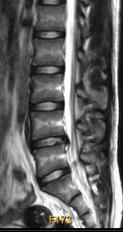

15岁的小王同学,在其母亲陈女士的陪同下来就诊。小王说,最近1月余来总感觉腰痛和左腿痛,一走路就加重,根本无法正常走路,呈跛行步态,陈女士见自己儿子小小年纪就这般难受,现在又是疫情期间,不知道如何是好,焦虑之际,经介绍,前来我院就诊,张昊主任医师予仔细、全面的查体,并阅读了相关影像学资料,经过团队的讨论,首先明确诊断为 “腰椎间盘突出症(L4/5 左侧)”。

针对该患者的诉求,张昊主任与其团队进行了反复的讨论并分析小王的问题,首先,小王才15岁,但腰椎间盘突出明确并伴有椎体后缘离断,神经受压明显,导致下肢疼痛、麻木,严重影响日常生活和学习,经过一段时间保守治疗,仍反复,并且越来越明显了,因此针对青少年的腰椎间盘突出症患者治疗方面该如何定夺呢?张昊主任分析,结合该患者的特殊性,又要考虑患者以后的影响,把相关治疗方案以及相应的风险等事宜详细告知陈女士,最终在微创理念下采用脊柱内镜下腰椎间盘摘除技术为小王进行手术,手术切口1cm,术后症状缓解,恢复良好,效果非常满意,第二天顺利出院。

术前影像